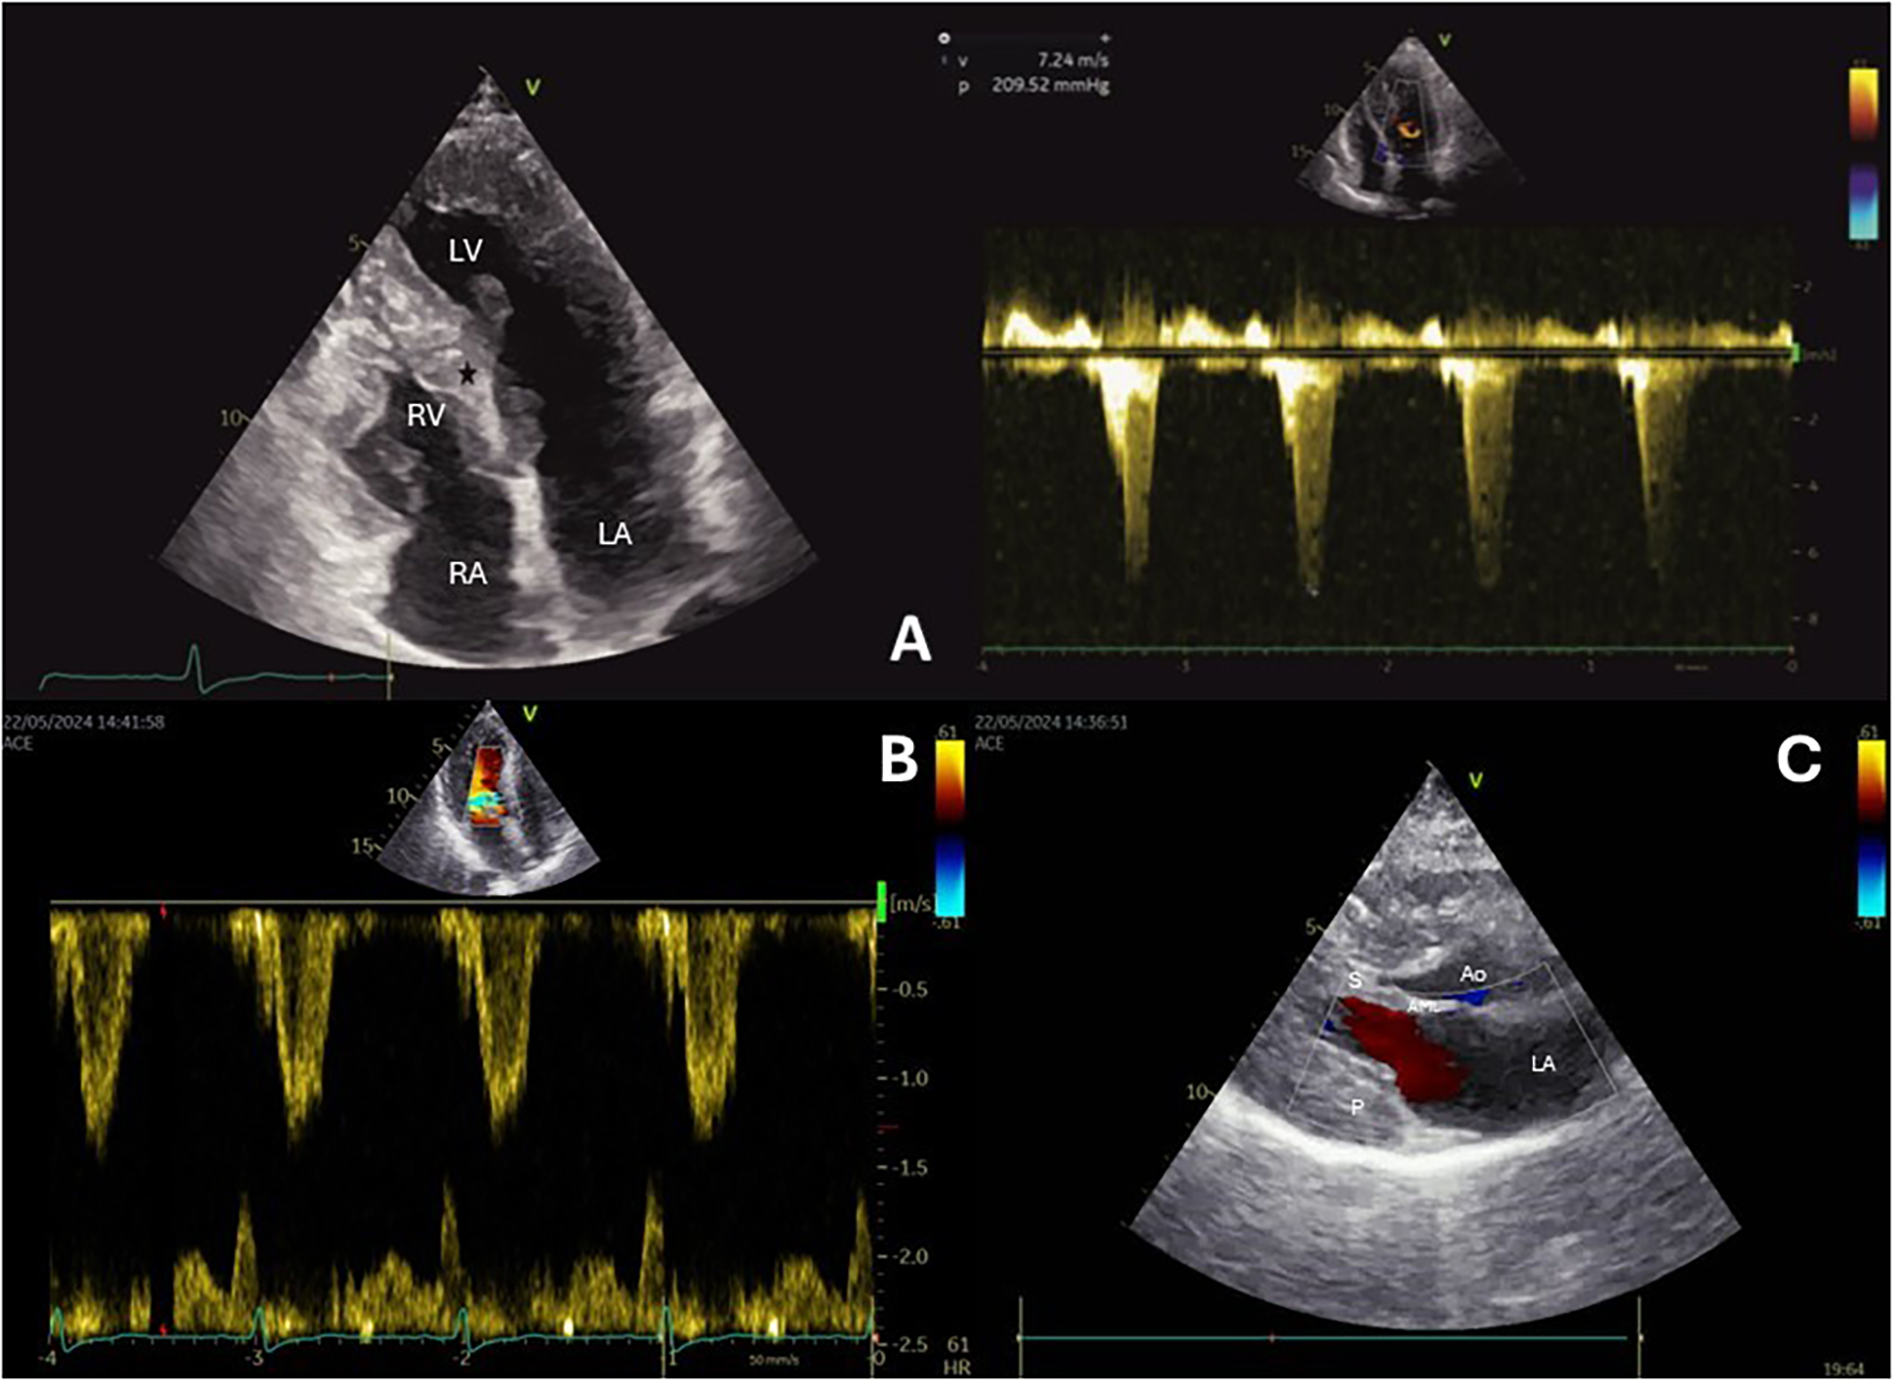

A 65-year-old female with a history of hypertension and asthma, presented with recurrent chest pain and severe fatigue and also experienced palpitations and dizziness. Echocardiography revealed concentric left ventricular hypertrophy with septal thickness of 20 mm, systolic anterior motion (SAM), LVOT obstruction and maximum gradient of 209 mmHg, measured during and immediately after the Valsalva maneuver (Figure 1A). Cardiac magnetic resonance (CMR) imaging confirmed echocardiography findings and transthyretin (TTR) amyloidosis and Anderson-Fabry disease were ruled out.

Figure 1

Echocardiography before the procedure (A) shows a hypertrophic basal segment of the interventricular septum (black star), and the continuous wave Doppler signal demonstrates increased LVOT velocity and gradient. After the procedure (B), echocardiography shows reduced interventricular septal thickness, and color Doppler reveals decreased velocity in the LVOT. Color Doppler echocardiography (C) reveals absence of mitral regurgitation.

On the second attempt, same guiding catheter and coronary guidewires were used. The embolization of septal branch was successfully done with two 2mm × 2 cm Azur Cx micro coil (Terumo Europe, Leuven, Belgium). (Figures 2A,B) During the procedure, echocardiography confirmed akinesia of the basal and mid septum, with a reduction in the LVOT velocities from 7.24 to 1.5 m/s, leading to a corresponding reduction in LVOT gradient from 209 mmHg to 9 mmHg. The procedure was completed successfully (Figures 1A–C), and the patient was discharged after 3 days with telemetry monitoring.